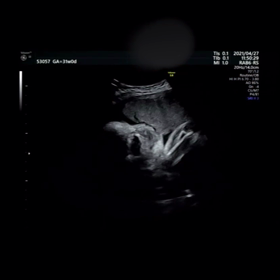

【4人目31wの健診】エコー動画と歴代4D写真

【4人目31wの健診】 エコー動画と歴代4D写真